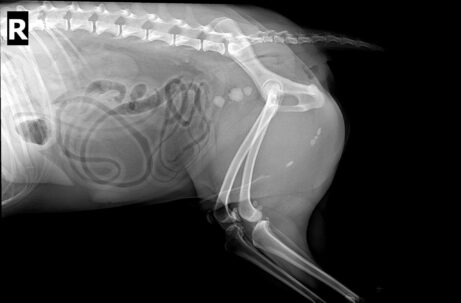

- diagnostika vývojových srdečních vad a onemocnění pomocí RTG, EKG A ULTRAZVUKU (Doppler)

- kontrastní RTG, rychlotesty

- vyšetření pomocí USG, RTG a endoskopu